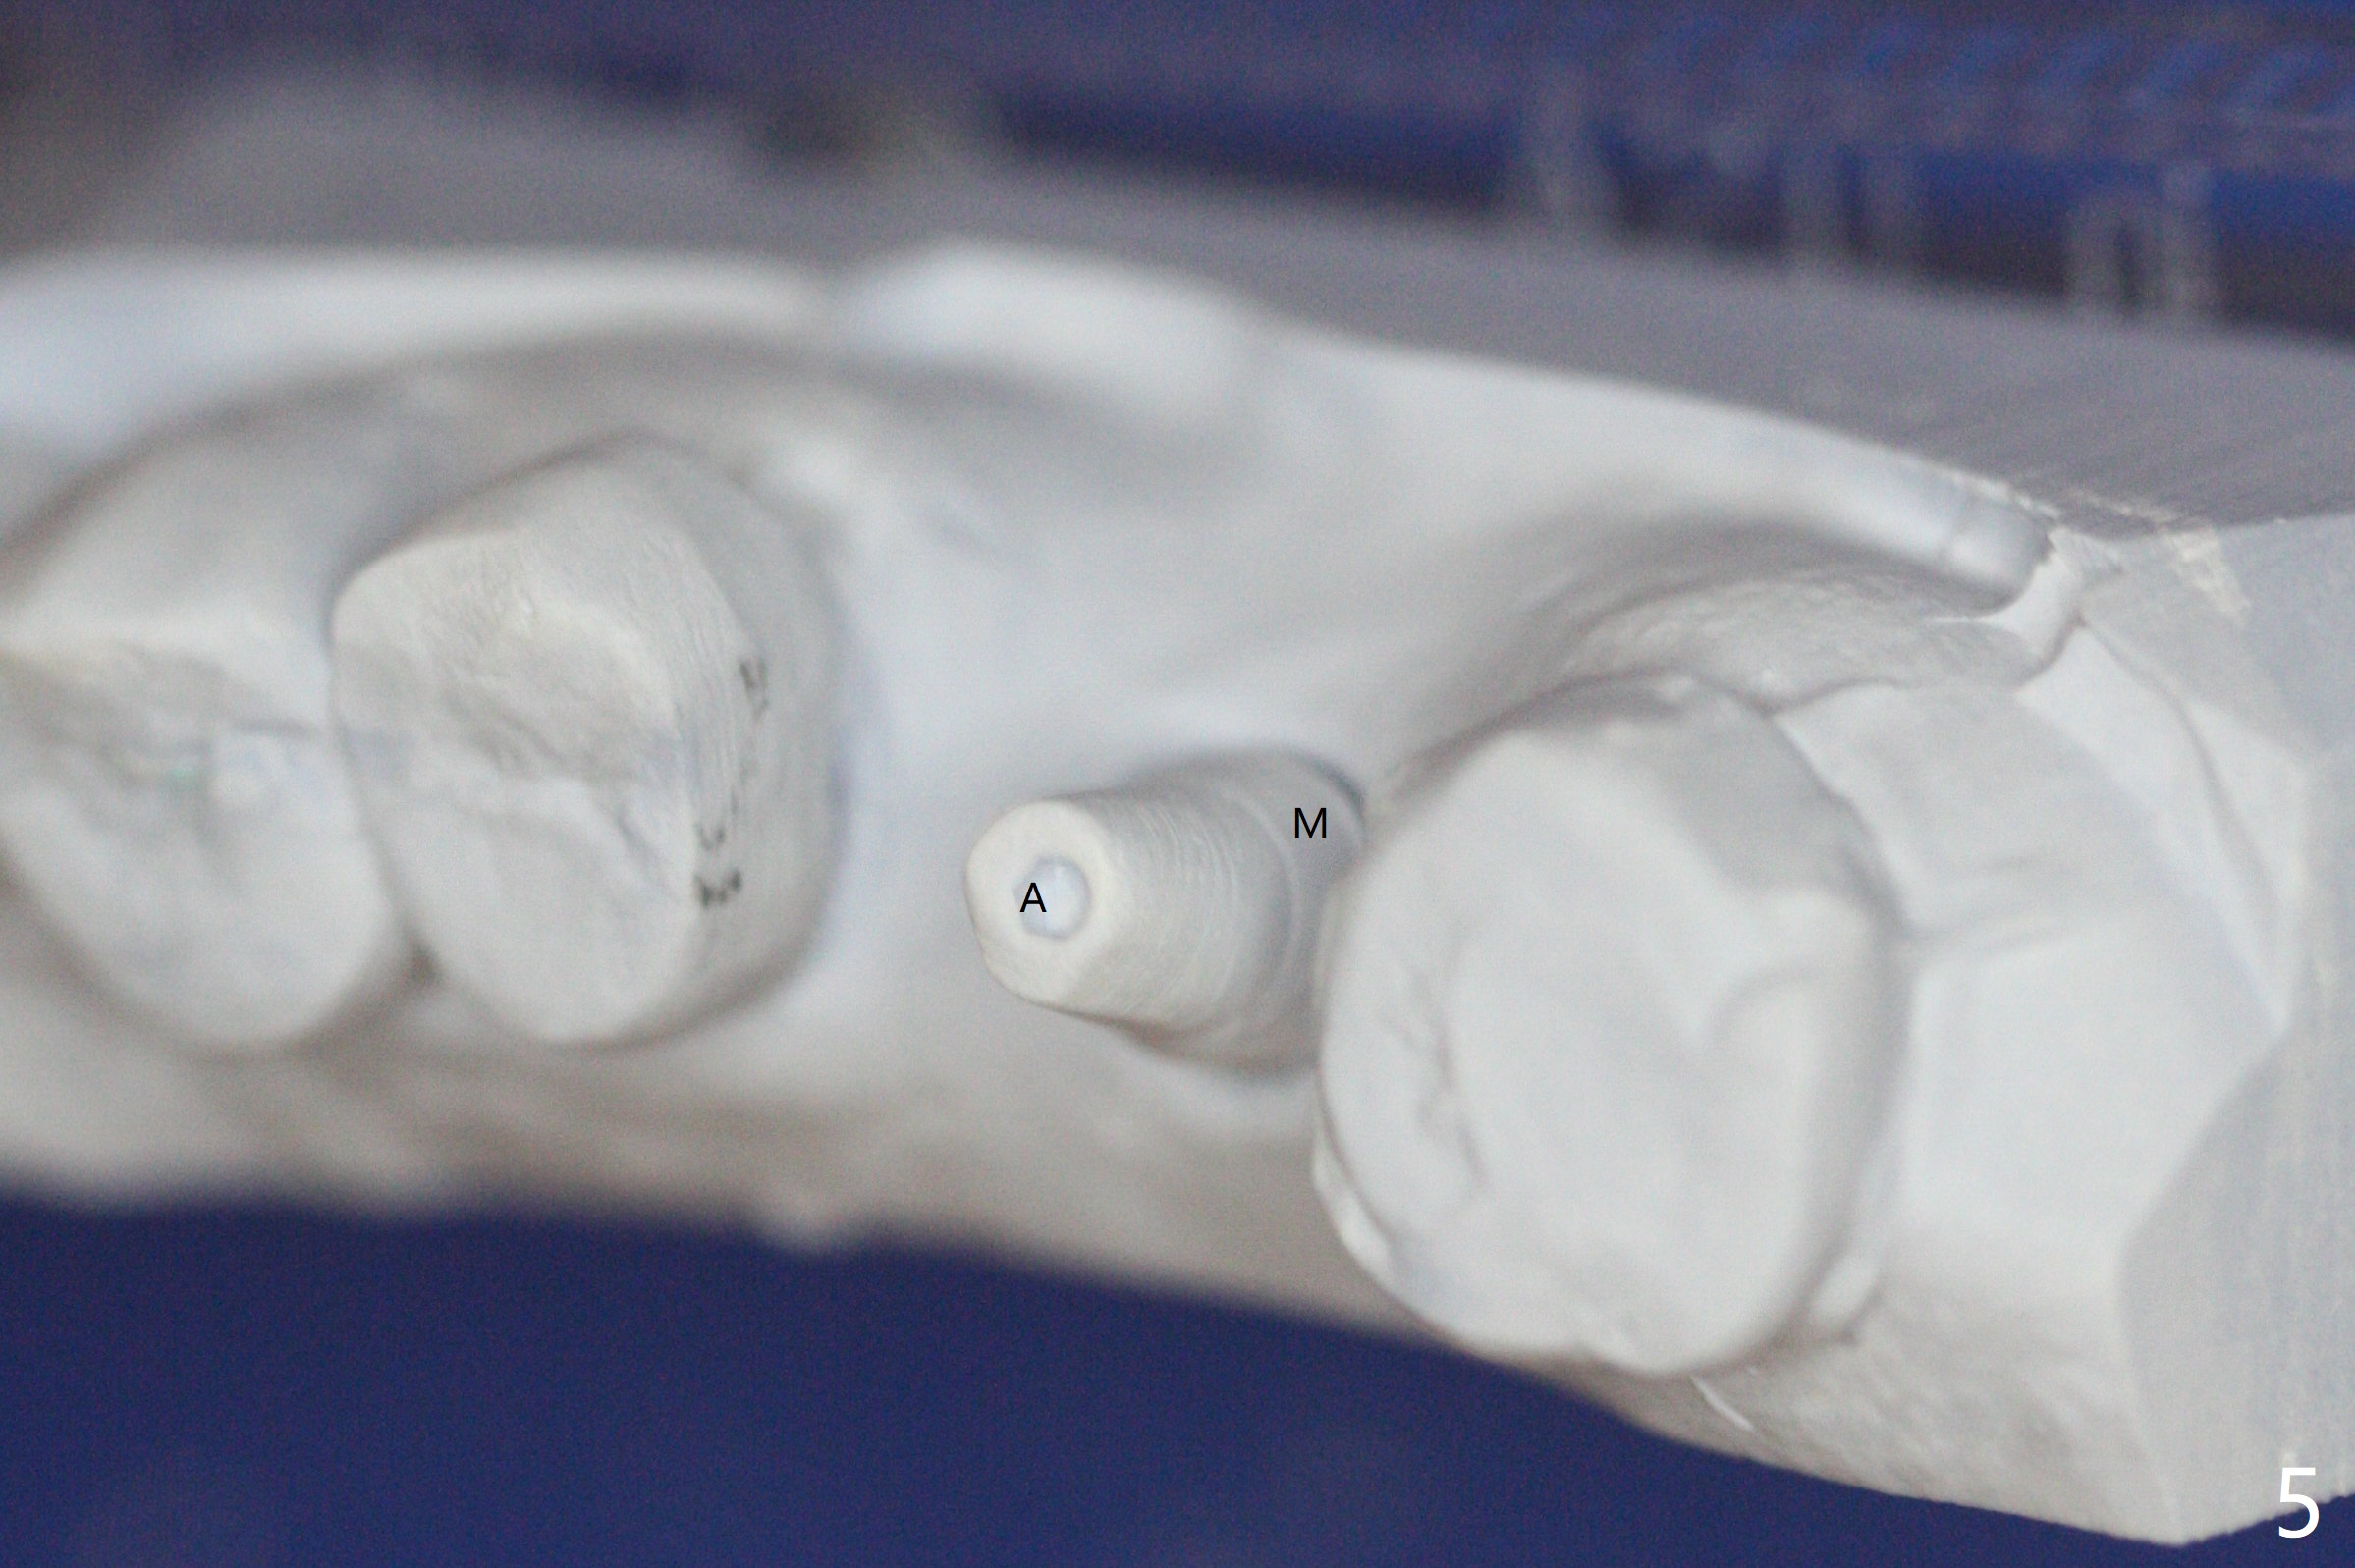

After 4.5x11.5 mm drill (10.5 mm offset) and 5.0 mm tap with guide at #14, the depth of the gingiva is measured 3 mm. A 5.5x9(3) mm Magicore cannot enter the green sleeve and is placed free hand (Fig.1). The margin is slight subgingival mesiodistal. With 3-4 turns, the buccal margin is slightly subgingival, while the palatal one slightly supragingival (Fig.2). The length of the implant could be 11 mm, considering the apical space (double arrows). To prevent periimplantitis, what is the appropriate placement depth coronally? Where does Titanium end? Dr. Wang thinks that the placement level is right. Probably due to underprep, the mesial crestal bone appears to have been resorbed 7 months postop (Fig.3 ^, as compared to Fig.1). The gingiva is healthy. A 4.3x5 mm solid abutment is torqued 20 Ncm for impression. The guide allows the implant to be placed lingual because of buccal concavity (Fig.4), but the coronal end of the solid abutment in the center for restoration (Fig.5 A). The crown is seated partially on the Magicore (M). The temp bond cemented crown is off 8 months post cementation (Fig.6). The bone density increases especially mesial.